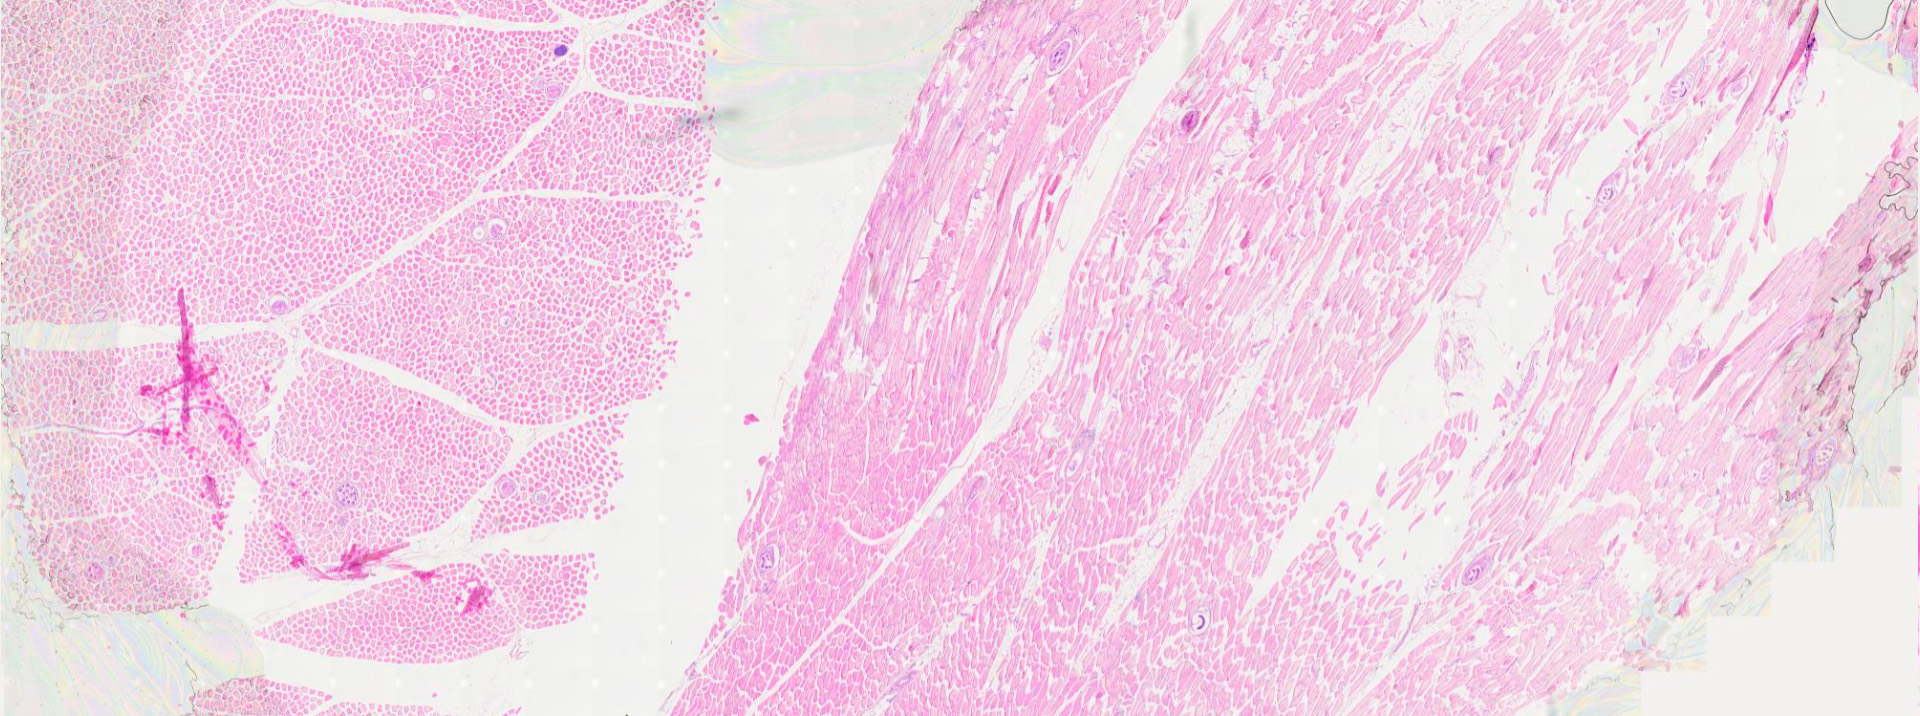

IMAGENES ESCANEADAS

Ascaris completo

Ascaris labios

Ascaris lumbricoides (Lombriz intestinal)

CARACTERÍSTICAS: El nematodo intestinal de mayor tamaño que parasita al ser humano. Es un geohelminto.

• Adulto (Macho y Hembra): Gusanos grandes, cilíndricos, de color blanco-rosado.

• Hembra: Mide 15–45 cm. Extremo posterior recto.

• Macho: Más pequeño, 15–30 cm. Extremo posterior curvado ventralmente, con espículas copulatorias. La boca en ambos sexos presenta tres labios prominentes.

UBICACIÓN: Adultos en la luz del intestino delgado (yeyuno). Larvas en migración (hígado, pulmones).